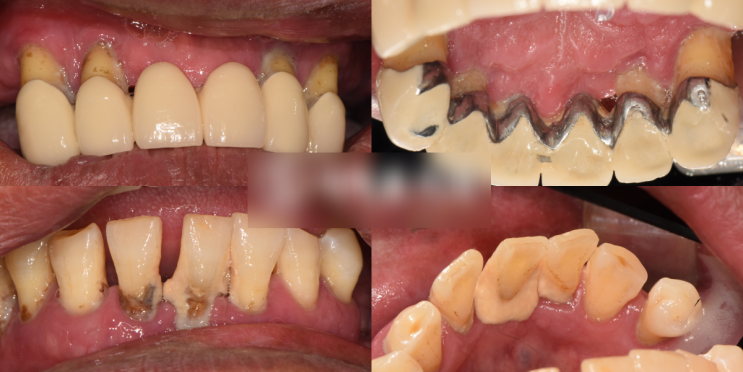

서대문구 치과 지속되는 치아 크라운 빠짐, 부러짐/ 앞니 뿌리 발치 후 임플란트 수술 과정

안녕하세요, 서대문구 치과 의사 조민기입니다. 만일 크라운 치료를 받은 부위에서 반복적으로 ‘빠짐’이...